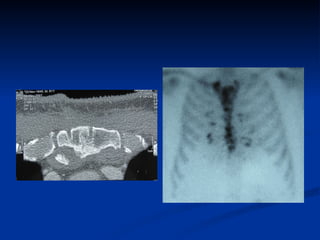

CT vs MRI Retrosternal Shadow Retrosternal Shadow

CT vs MRIRetrosternal Shadow Retrosternal Shadow